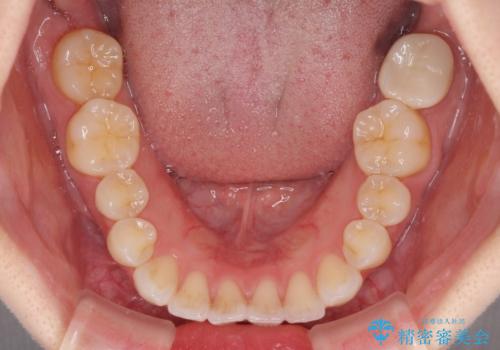

- 矯正治療の後戻りを気にして来院された患者様です。

後戻りは軽微でしたが、舌突出癖が認められ、初診時には上下前歯に舌がはまるスペースができていました。

舌突出癖の改善を行いながら、インビザライン・ライトにより矯正治療を行うこととしました。

舌突出癖の改善により上下前歯が接触するようになり、前歯でものを咬みきる必要のある食事がスムーズに行えるようになりました。